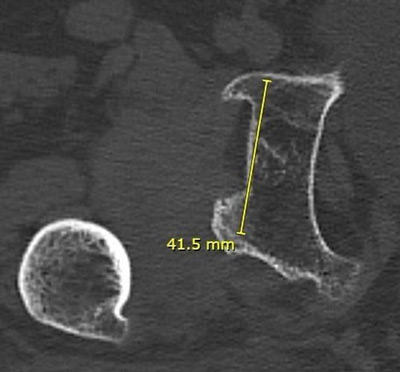

Pre-operative X-rays and CT-scan

Management of a hip dysplasia in a middle-aged woman:  Pre-operative X-rays and CT-scan